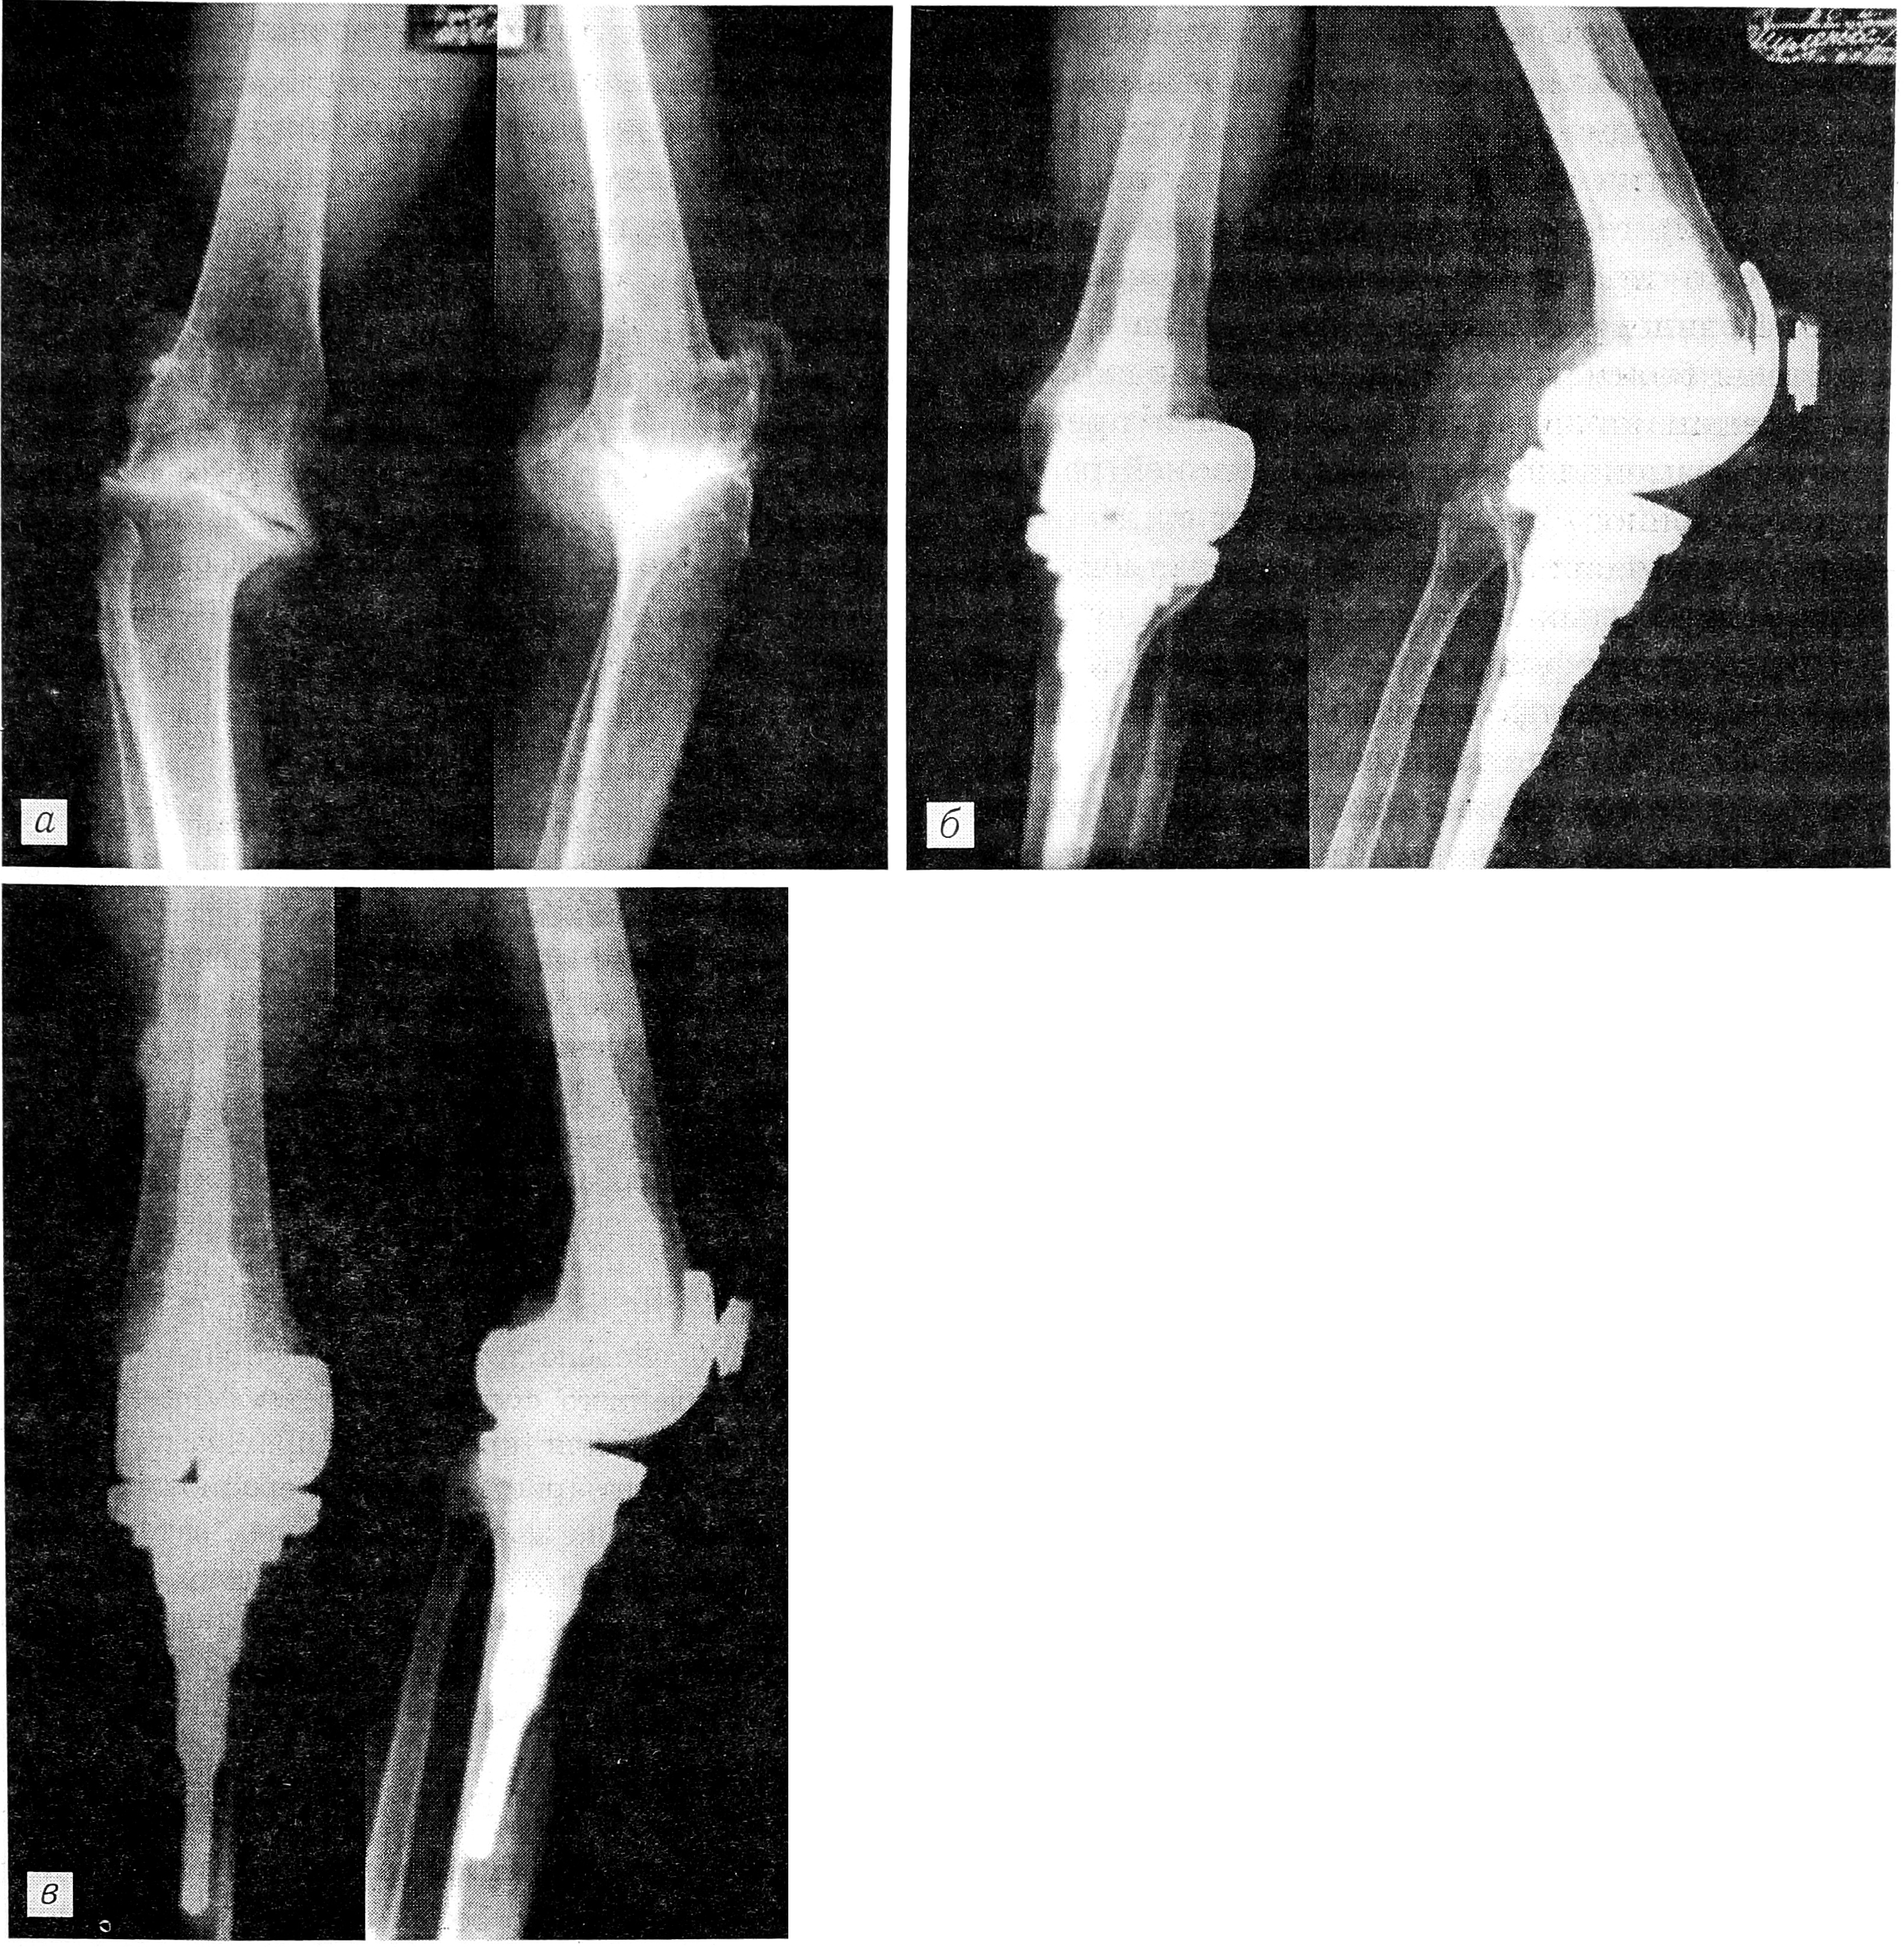

В качестве иллюстрации приводим случай успешного двустороннего тотального эндопротезирования коленных суставов.

Больная Ш., 1918 года рождения, впервые обратилась в ЦИТО в 1990 г. с жалобами на боли в обоих коленных суставах, деформацию, нарушение опорности конечностей. Выявлены двусторонний гонартроз III стадии, контрактура обоих коленных суставов, варусная деформация (рис. 1, а). Больна в течение 30 лет. В 1988 г. произведена операция — лавсанопластика передней крестообразной и внутренней боковой связок правого коленного сустава. Боли в суставе продолжали беспокоить.

В 1991 г. в ЦИТО выполнено тотальное эндопротезирование левого коленного сустава протезом «ЕСКА medical» (рис. 1, б). Послеоперационный период протекал без осложнений, рана зажила первичным натяжением. Больная выписана домой через 3 нед после операции. При выписке болей в суставе нет, ось конечности восстановлена, контрактура в коленном суставе устранена, сгибание увеличилось до 90°.

В 1994 г. больная повторно госпитализирована в ЦИТО с жалобами на боли в правом коленном суставе. При осмотре определяются деформация сустава, варусное отклонение голени, контрактура под углом 170°, сгибание в суставе до 150°. В июне 1994 г. произведено тотальное эндопротезирование правого коленного сустава протезом «Intermedics- Orthopaedics», для крепления протеза применен костный цемент (рис. 2). Послеоперационное течение гладкое. Рана зажила первичным натяжением. Больная выписана из отделения через 3 нед после операции. При выписке болей в суставе нет, деформация и контрактура устранены, сгибание в обоих коленных суставах в пределах 180—90°. При осмотре через 6 мес жалоб не предъявляет, ходит без дополнительных средств опоры (рис. 1, в).

Рис. 1. Рентгенограммы левого коленного сустава больной Ш. (прямая и боковая проекции).

a — до эндопротезирования; б — непосредственно после тотального эндопротезирования протезом «ЕСКА medical»; в — через 3 года после эндопротезирования.

Рис. 2. Рентгенограммы правого коленного сустава той же больной Ш. после тотального эндопротезирования протезом «Intermedics-Orthopaedics» (прямая и боковая проекции).